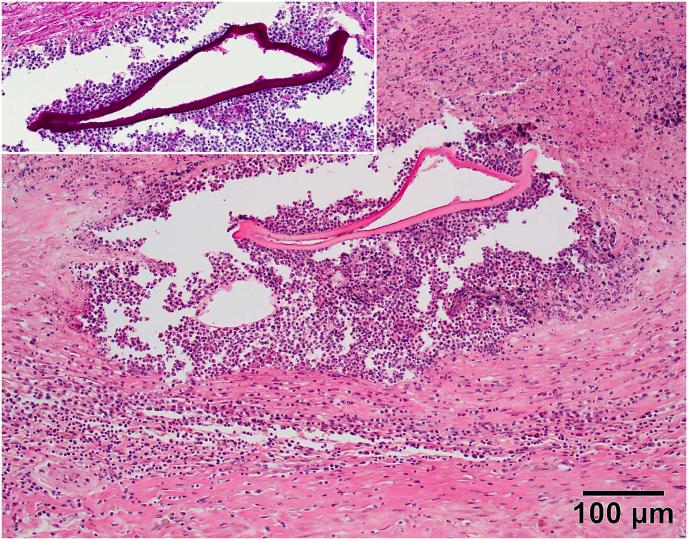

While the principle definitive host of the zoonotic cestode in Europe is the red fox, several rodent species act as main intermediate hosts. Among others, e.g., humans, dogs, and pigs, also horses have been described to act as aberrant hosts in highly endemic regions. Here, a case of an infection in a kulan () is described. The five years old kulan from a zoo in Slovakia was transported to an animal park in Germany. The animal had to be euthanized within a few weeks after the import due to its poor general state of health. The pathological examination revealed a nodular mass in the liver as an incidental finding. By histological examination of the mass, a pyogranulomatous and necrotizing inflammation and intralesional fragments of amorphous eosinophil layers were detected. The suspected diagnosis of infection was confirmed by PCR addressing parts of the genes 12S rRNA and the NADH dehydrogenase subunit 2, showing very high identities with isolates from France, Slovakia and the USA.

虽然欧洲人畜共患绦虫的主要终末宿主是赤狐,但几种啮齿动物物种是主要中间宿主。除此之外,例如人类、狗和猪,在高流行地区马也被描述为异常宿主。在此,描述了一例在印度野驴身上的感染病例。这头来自斯洛伐克一家动物园的5岁印度野驴被运到德国的一个野生动物园。由于其总体健康状况不佳,这头动物在进口后几周内不得不实施安乐死。病理检查偶然发现肝脏中有一个结节性肿块。通过对肿块进行组织学检查,检测到脓性肉芽肿性和坏死性炎症以及病灶内无定形嗜酸性层碎片。通过针对12S rRNA基因部分和NADH脱氢酶亚基2的PCR确诊了疑似的感染,显示与来自法国、斯洛伐克和美国的分离株具有非常高的同源性。